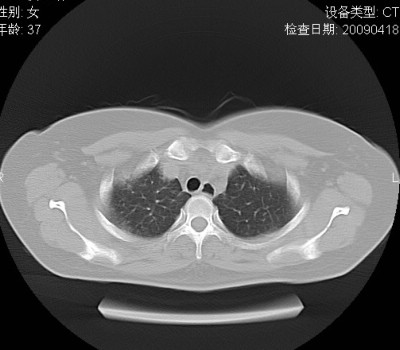

以下是引用随光逐影在2009-4-20 8:03:00的发言:[br]两肺间质性病变(间质性肺炎?特发性肺间质纤维化?)。

以下是引用51736011在2009-4-21 16:24:00的发言:[br]两肺间质性病变(间质性肺炎?特发性肺间质纤维化?)。